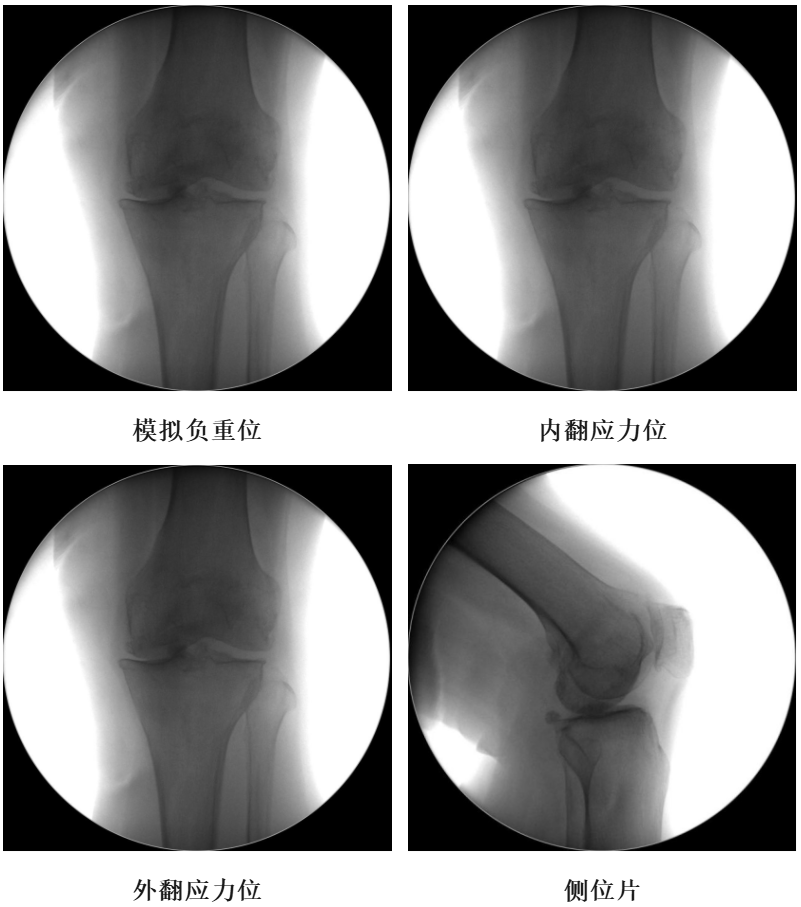

术前透视片